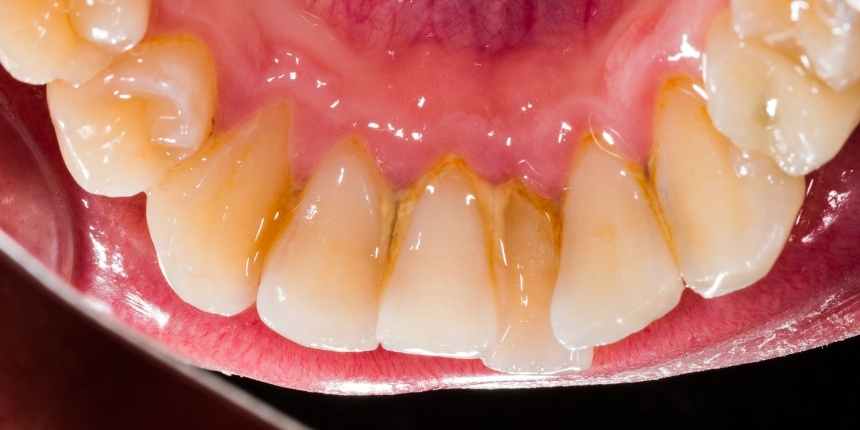

Quando a higiene bucal não é feita corretamente, essa placa se transforma em uma camada dura, de cor amarelada ou acastanhada, que adere com firmeza à estrutura dentária.

- Tártaro supragengival: Formado acima da linha da gengiva, geralmente visível e mais fácil de identificar. Costuma aparecer na superfície interna dos dentes inferiores e nas margens gengivais.